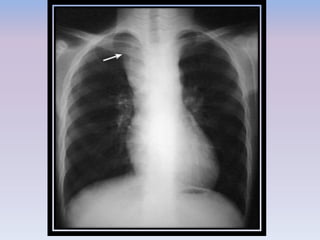

DEEP SULCUS SIGN

• The deep sulcus sign describes the radiolucency extending from the lateral

costophrenic angle to the hypochondrium

• It is an important clue indicating possible pneumothorax in chest x-rays obtained in

the supine position.

• When plain films are taken with the subject in an upright position, the free air in the

pleural space gathers at the apicolateral space.

• In the supine position, the air accumulating at the anterior space forms a triangular

radiolucency that makes the inferior borders of the lateral costophrenic angle

conspicuous

DEEP SULCUS SIGN •The deep sulcus sign describes the radiolucency extending from the lateral costophrenic angle to the hypochondrium • It is an important clue indicating possible pneumothorax in chest x-rays obtained in the supine position. • When plain films are taken with the subject in an upright position, the free air in the pleural space gathers at the apicolateral space. • In the supine position, the air accumulating at the anterior space forms a triangular radiolucency that makes the inferior borders of the lateral costophrenic angle conspicuous